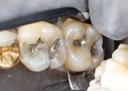

Wayne Chin #30 pre-op

Wayne Chin #30 amalgam removal